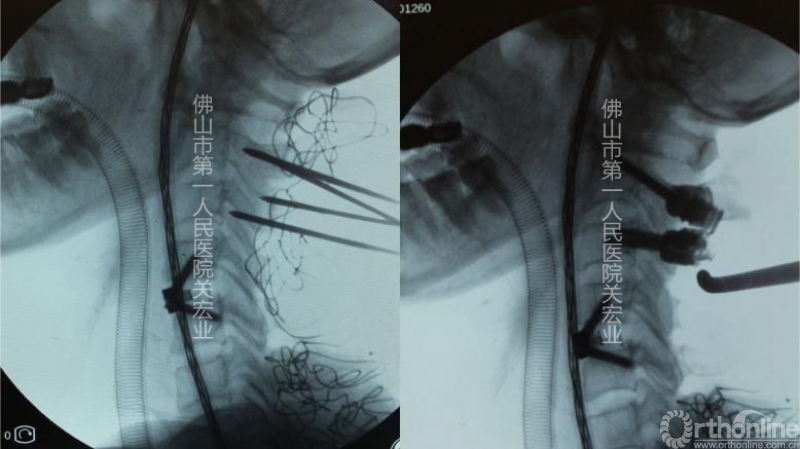

术中置钉与定位